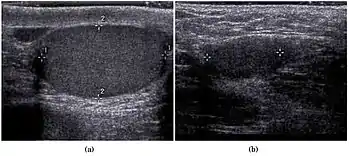

| کریپتورکیدیسم در سونوگرافی بیضه. | |